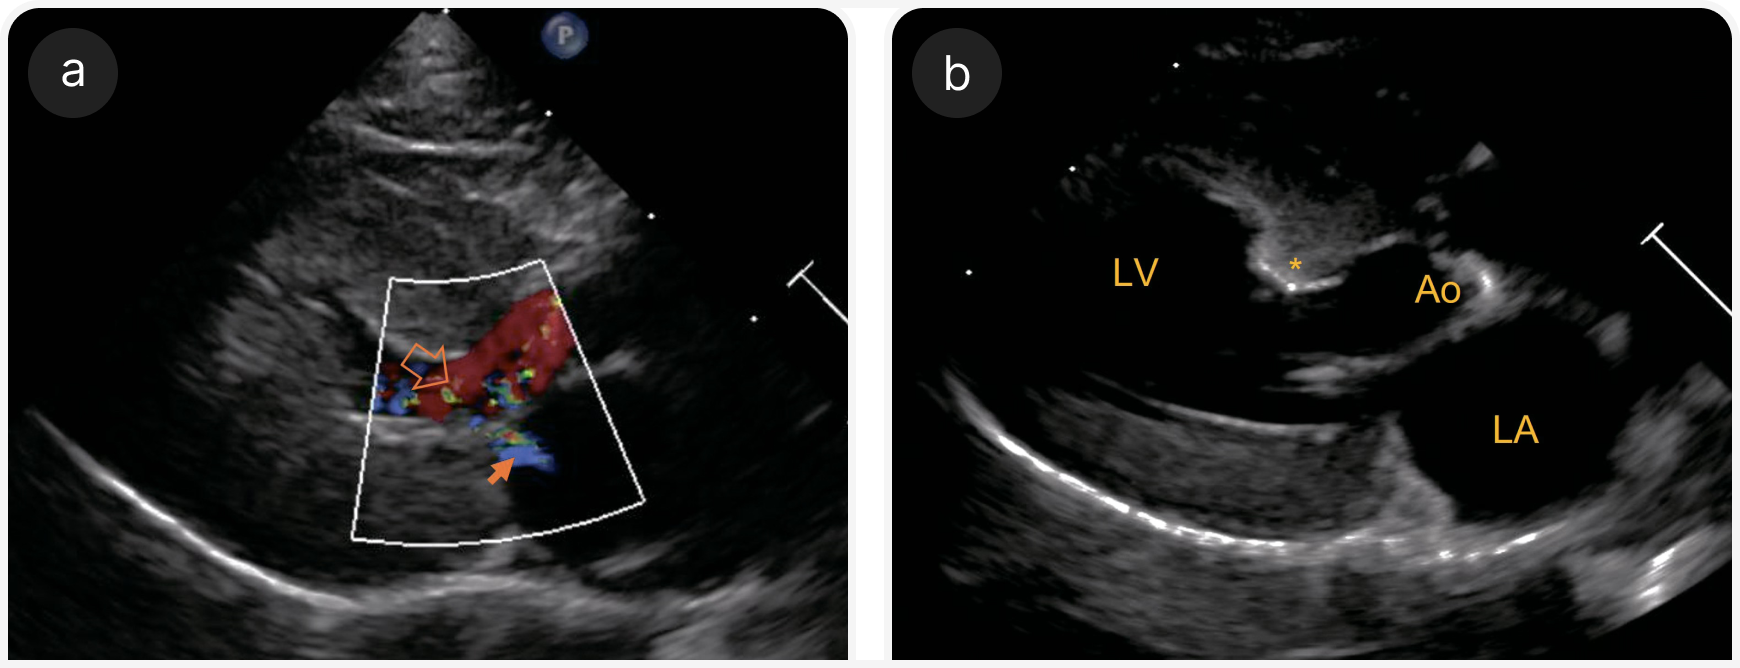

У части кошек с ГКМП возможна значимая обструкция ВТЛЖ (Рисунок 3). Такие случаи классически назывались гипертрофической обструктивной кардиомиопатией (ГОКМП), но в медицине человека от этого термина отказались, поскольку обструкция ВТЛЖ может быть периодической; это соображение верно и для кошек, поэтому термин ГОКМП, по всей вероятности, является устаревшим (3, 9, 11). Обструкция ВТЛЖ может быть результатом SAM (систолическое смещение передней створки митрального клапана кпереди), очаговой гипертрофии базальной перегородки или, реже, обструкции средней части полости ЛЖ из‑за гипертрофии папиллярных мышц (4, 9, 12).

Обструкция ВТЛЖ вызывает шум из‑за повышения турбулентности потока крови. При SAM обструкция обычно динамическая, то есть увеличивается при повышении сократительной способности мышцы сердца, например во время физического или эмоционального стресса. Это часто становится причиной вариабельности в наличии или интенсивности шумов у кошек с ГКМП.

SAM возникает, когда септальная (передняя) створка (часто удлиненная) в результате гипертрофии и смещения папиллярной мышцы оттягивается к выходному тракту, что приводит к провисанию хордальных сухожилий (10). По мере сужения выходного тракта в результате такого аномального движения створки (или гипертрофии базальной перегородки) скорость крови увеличивается, а давление снижается, увлекая верхушку створки дальше в выходной тракт и усугубляя обструкцию (эффект Вентури) (4, 9).

3. Наличие обструкции ВТЛЖ

Обструкцию ВТЛЖ можно оценить с помощью двухмерной эхокардиографии, в М-режиме, при допплерографии с цветовым картированием потока и спектральной допплерографии (Рисунок 3c). SAM можно визуализировать как в двумерном, так и в М-режиме. При допплерографии с цветовым картированием потока определяют турбулентность в ВТЛЖ и, возможно, митральную регургитацию. При спектральной допплерографии возможно оценить скорость кровотока через ВТЛЖ , если поток хорошо визуализируется; при динамической обструкции в допплерографическом профиле часто выявляют двухфазное ускорение (в форме классической турецкой сабли — ятагана).